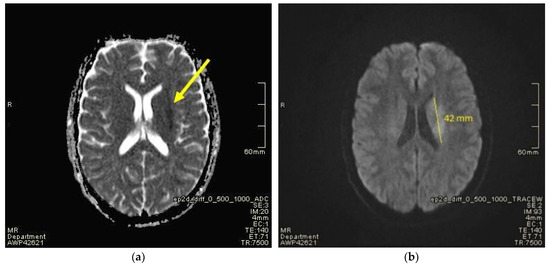

2. Case Presentation